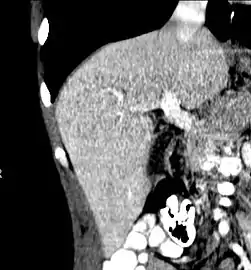

After resection of left lobe liver tumor

Liver transplantation is the only option for those with irreversible liver failure. Most transplants are done for chronic liver diseases leading to cirrhosis, such as chronic hepatitis C, alcoholism, and autoimmune hepatitis. Less commonly, liver transplantation is done for fulminant hepatic failure, in which liver failure occurs rapidly over a period of days or weeks.